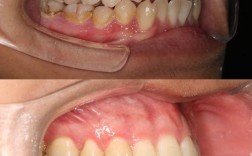

- 牙根形态与长度评估:通过根尖片或CBCT(锥形束CT)检查牙根形态,观察是否存在锥形牙根、弯曲牙根、牙根过短或牙根吸收史(如既往创伤、正畸史导致的吸收),CBCT可三维重建牙根结构,清晰显示牙根表面是否有凹陷、吸收陷窝等,比传统根尖片更敏感。

- 牙周状况检查:牙周健康是牙齿移动的基础,需评估牙龈指数、牙周袋深度、牙槽骨高度等,若存在牙周炎(牙槽骨吸收超过根长1/3),需先进行牙周治疗,控制炎症后再开始正畸,避免炎症状态下牙根移动加重吸收。